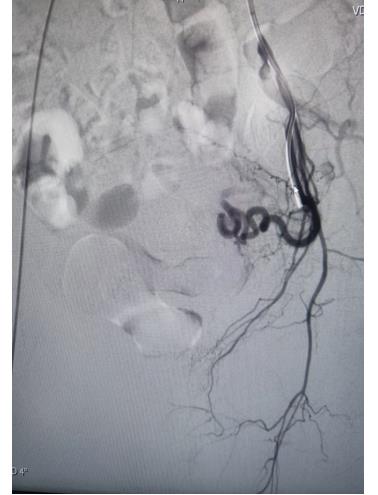

冠脈手術后